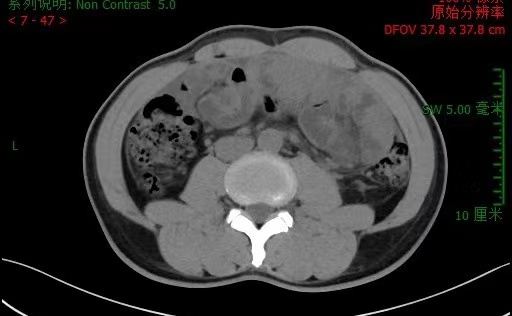

图说: 李先生入院腹部CT 采访对象供图(下同)

南院区普外科检查及会诊后发现,患者左下腹有一个25*20cm的硬质包块活动度差,有局限性压痛、反跳痛;CT检查显示小肠系膜纠集,周围线状包裹,提示“腹茧症可能,伴小肠不全梗阻”;患者肿瘤标志物、结核指标、自身免疫指标、胃肠镜等检验检查均为阴性。经讨论后,大家一致认为,造成李先生呕吐、腹痛、停止排便的“元凶”是腹茧症,患者小肠被纤维包膜层层包裹,失去蠕动的功能,因此演化为不完全性粘连性肠梗阻。手术剥离肠管外周增厚的纤维膜是解除梗阻、恢复正常进食的唯一途径。